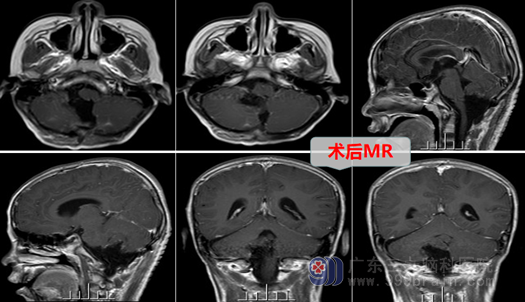

看着病倒在床上的儿子,踌躇了许久,小辉父母商量后,决定直面困境。神经外十科手术团队仔细查看患者影像检查,经过术前讨论,制定了慎密的手术方案,在全麻下行右侧后颅窝开颅行小脑肿瘤切除术。手术过程顺利,一举两得:医生不仅切除了肿瘤,又没有影响到患儿的正常功能,肿瘤病理结果为低级别胶质瘤。

术后,小辉恢复良好,没有出现任何神经功能障碍。出院时,小辉父母非常高兴,激动地写下感谢信,感谢外十科医疗及护理团队,并表示会定期前来复查,按计划完成后续的综合治疗。